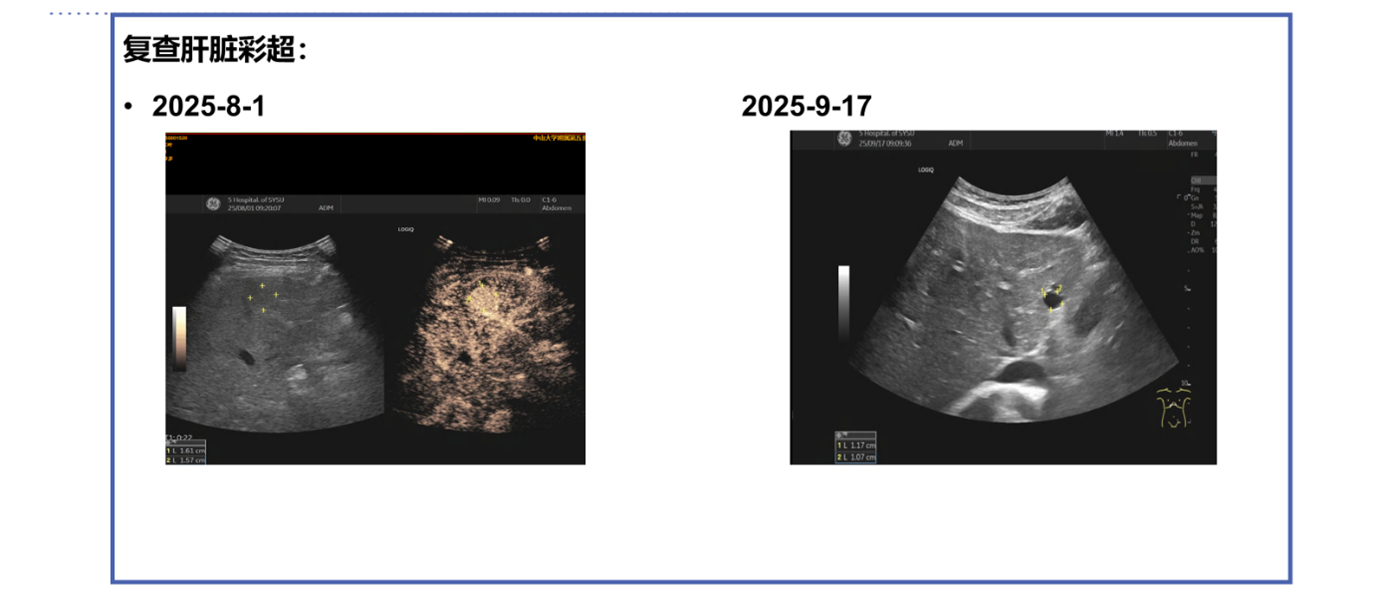

2025年7月,即术后3年7个月,患者在门诊复查时发现病情进展。上腹部MRI及超声造影均提示肝脏S4出现新发结节,高度提示转移瘤 。

该方案疗效显著: 2025年9月17日进行了第一周期疗效评估,复查超声即显示肝S4病灶回声增强,体积从15×14mm缩小至10×8mm。根据RECIST标准,疗效评估为部分缓解(PR)。

治疗3个月后(2025年11月13日),复查上腹部增强MRI显示,肝S4主病灶进一步缩小至8mm,且增强后各期强化不明显,提示肿瘤活性受到抑制。

本例患者在接受含伊那利塞的四药联合治疗后,呈现了与临床研究结果相一致的快速缓解特征:治疗1个月余时,超声检查即提示病灶回声增强、体积缩小 ;治疗3个月时,MRI进一步确认肝S4主病灶从基线的15mm缩小至8mm,且增强扫描未见明确强化,提示肿瘤活性受到抑制 。这种“快速起效、深度缓解”的临床表现提示,以伊那利塞为核心的联合方案是应对高肿瘤负荷及内脏转移患者的优选策略之一。